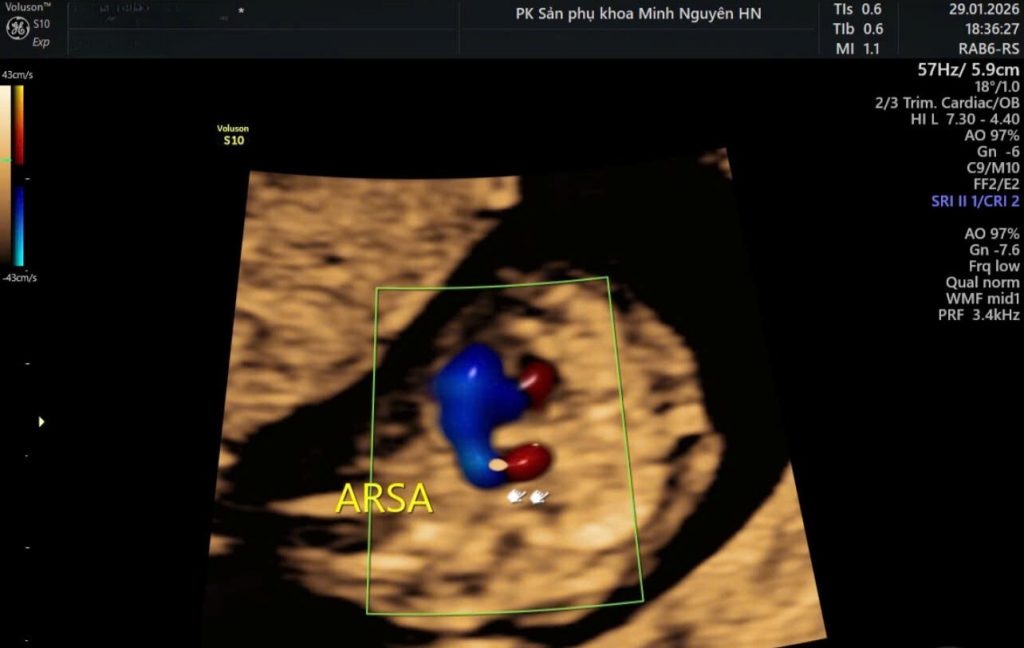

Động mạch dưới đòn phải lạc chỗ ARSA được phát hiện ở mặt cắt ba mạch máu và khí quản khi siêu âm tim thai.

Khi sử dụng Doppler màu, bác sĩ sẽ thấy một nhánh mạch đi từ phía sau khí quản sang phải. Đây là dấu hiệu đặc trưng.